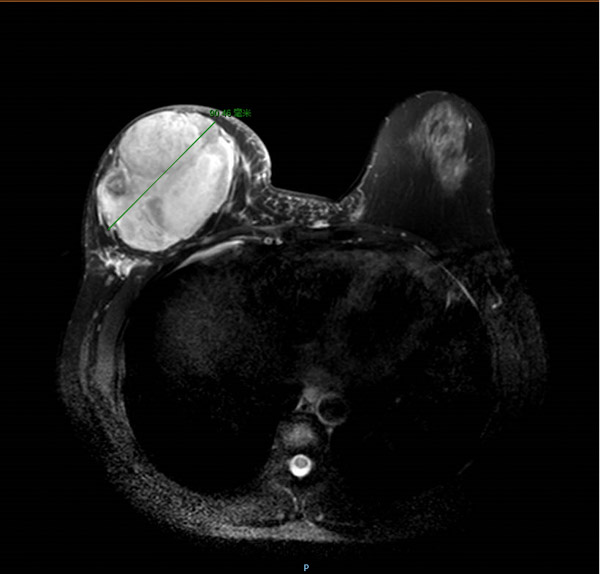

经过完善而系统的检查,结合病史、查体及辅助检查,主诊医生覃舒婷副主任医师考虑谭女士右乳肿瘤为乳腺叶状肿瘤复发,建议行手术治疗。可在这时,原本有着坚定手术意愿的她却动摇了,因为医生的建议是右乳乳腺的全部切除!“为什么我的乳房要全部切掉!”不解的谭女士及家属来到医生办公室询问,覃医生耐心地为患者解答了疑惑,结合磁共振影像,谭女士明白了,磁共振图像上,右乳内近10cm的巨大肿瘤,已经将正常腺体组织压迫到所剩无几,残余的腺体不仅不能支撑一个正常的乳房,还可能再次复发。